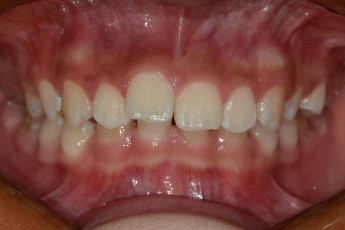

BEFORE & AFTER

- 덧니교정

- 매복치교정